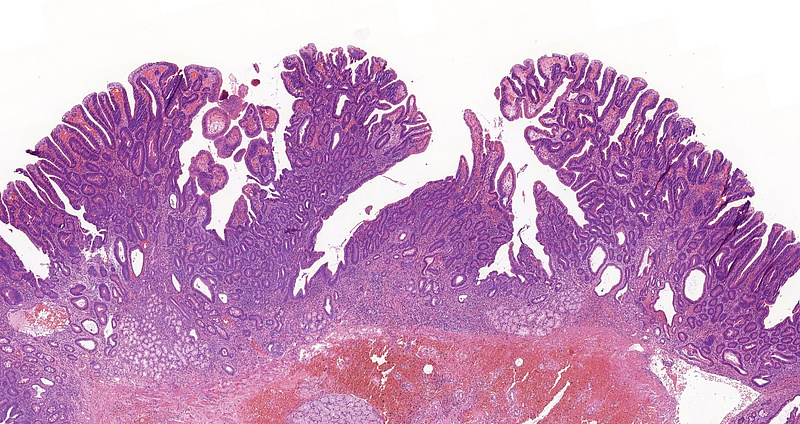

A 60-year-old female patient underwent multiple gastroscopies during the last 5 years because of recurring jaundice. Biopsy samples of the Vater papilla were taken each time, showing tubular or tubulovillous adenomatous growth. In 2021, the lesion was resected in toto with sphincteroplasty. Microscopic examination of this sample revealed tubular and tubulovillous structures, showing signs of low-grade dysplasia (revised Vienna classification category 3) in continuation with normal mucosa [Panels A-D]. Brunner glands were present in the submucosa. Even though the resection margin was free of dysplasia and invasive malignancy not detected, careful follow-up was recommended due to the patient’s history and the recurring nature of the lesion.